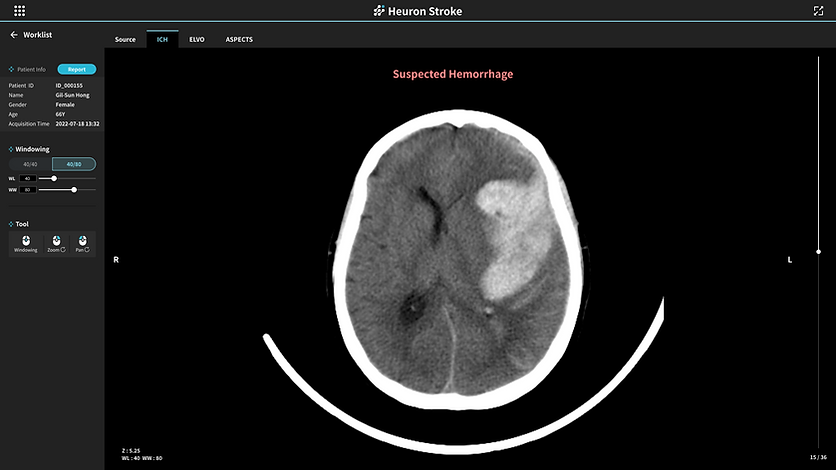

Heuron ICH

.png)

Non - Contrast CT Based AI Solutions For The Early Screening Of Hemorrhagic Stroke

Identification of intracerebral hemorrhage